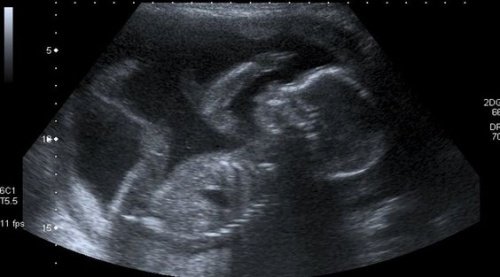

Bir kadın ilk ultrason işlemi sırasında gerçekten artık bir anne olduğunu anlar. Çocuğunun hızlı kalp atışlarını duyunca duygulanır ve gözyaşlarını tutamaz. Kalbi hızlıca atar ve henüz doğmamış bebeği ile kurduğu bu ilk temastan dolayı sevince boğulur.

Önündeki dokuz ay boyunca; oğlu ya da kızıyla yüz yüze gelip, cildinin, saçının ve gözlerinin rengini keşfetmeden önce, siyah-beyaz bir ekranda bulanık ultrason görüntüleriyle yetinmek zorunda kalır.